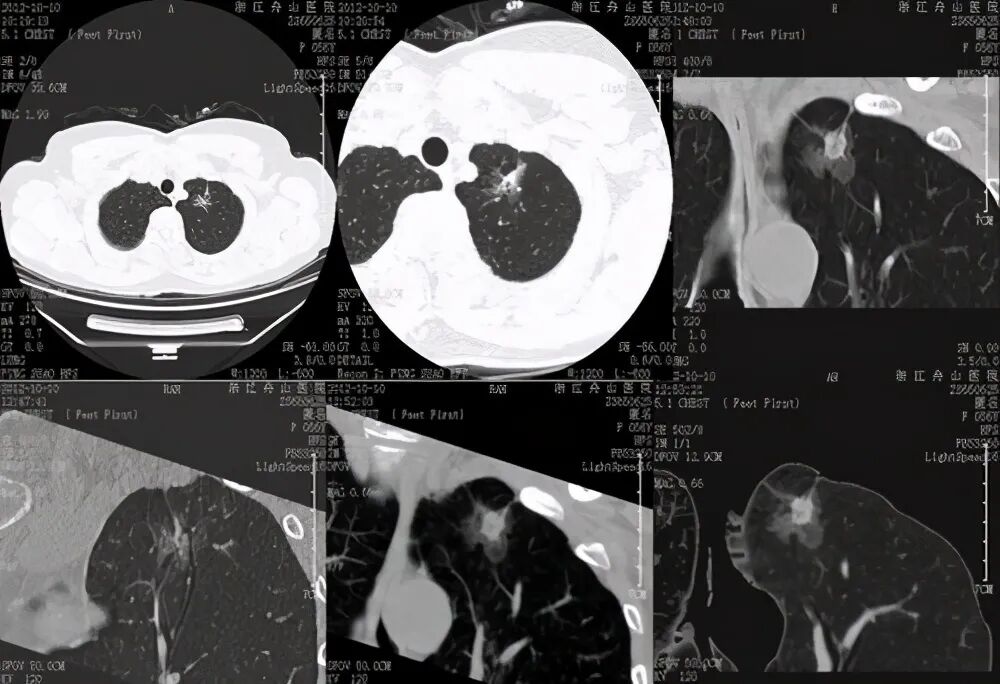

常规胸部CT扫描由于视野大、层厚较厚,不能全面观察肺结节影像特征。靶扫描又称放大扫描、感兴趣区扫描,是针对肺部<3cm的病灶,也就是我们所说的“肺结节”所进行的小范围局部扫描。简而言之,就是肺部CT检查时以小视角、小范围的扫描,扫描范围小于全肺,优势在于可以薄层地找到病灶并放大病灶。

靶扫描可以更全面、多方位、更直观地观察病灶的形态、特征,观察病灶边缘、中心结构,然后通过计算机处理和医生的经验去发现有价值的诊断线索,从而得出更为准确的结论。靶扫描通过提高空间分辨率,更好地显示肺结节病变特征,为肺内结节的定性诊断提供更多的依据。

肺部充满气体,属于具有良好自然对比的脏器,但肺脏不停地呼吸运动,做CT时容易受到呼吸运动的影响,靶扫描使用小范围、薄层技术采集到的小体积像素对呼吸运动伪影具有几何放大的作用,也就是说极大减少了呼吸运动伪影。